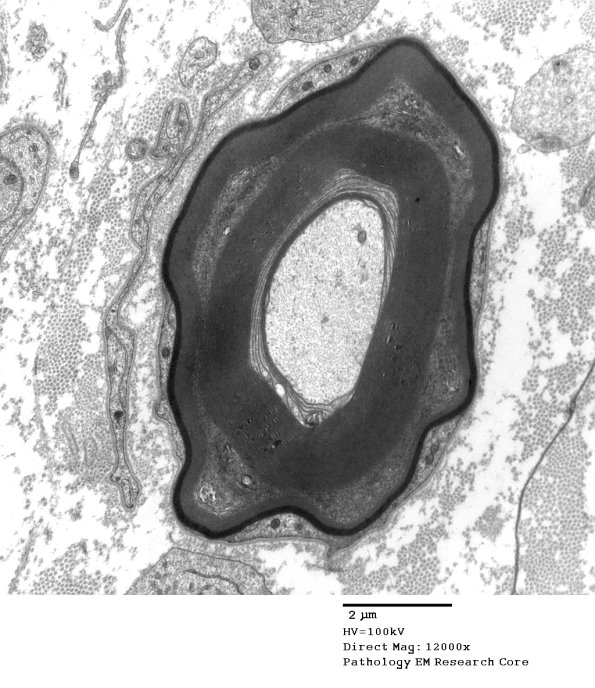

In this case, although there is a completely demyelinated axon the other axon would be too borderline to call.